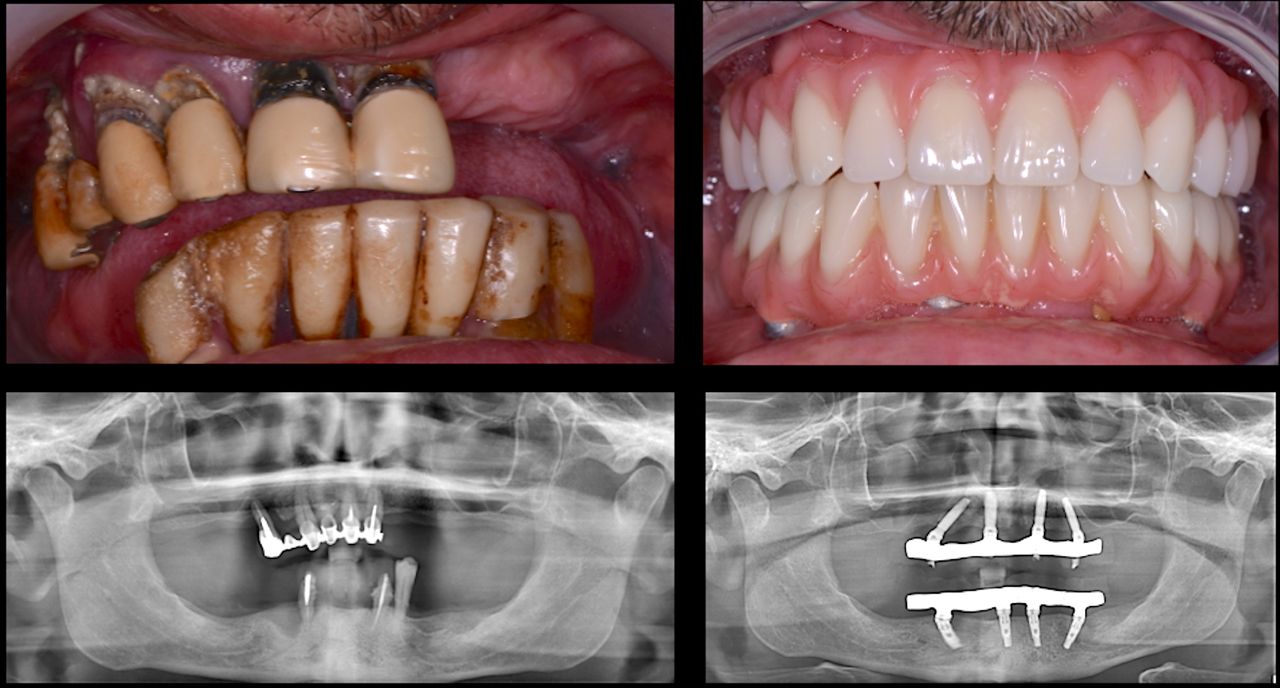

Foto e video